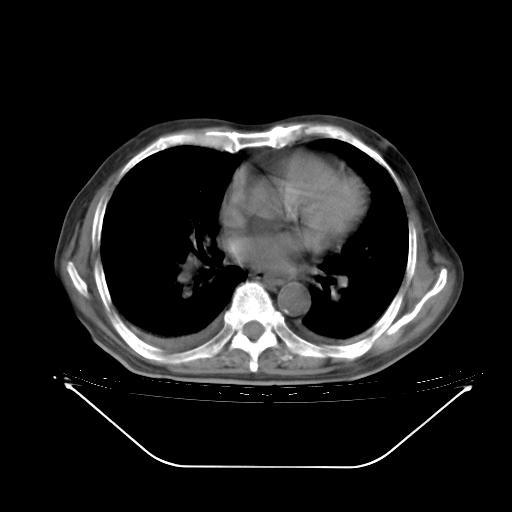

5月9日肺部CT(在4月27日齐鲁医院肺部CT描述部分肺组织磨玻璃样改变,12天后肺组织广泛磨玻璃样改变)

2009年5月9日肺部CT

大致读了系列胸部CT:纵隔窗无明显异常,肺窗:从4、27至今:主要是双肺中下野外带可见毛玻璃样改变,目前处于急性肺泡炎阶段,至于原因考虑1、结替组织或胶原血管性疾病所致?2、恶性疾病如恶组在肺部所致的表现或细支气管肺泡癌?3、药物或其它原因如肺蛋白沉着症所致肺泡炎目前不太可能?总之,明天就去请我院的呼吸科、感染科、血液科和临免专家会诊哈。